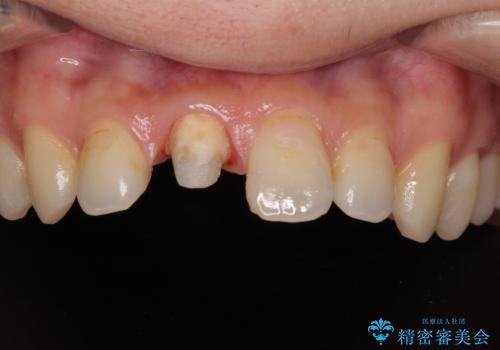

- 数年前に前歯のセラミック治療を行い、そのやり替えを希望して来院された患者様です。

先端が欠けてしまっていて、色も少し不自然な印象があります。

空隙がある歯並び改善のため、矯正治療も提案しましたが希望せれず、隣の歯も一緒に被せものにして、

大きさをそろえることも希望されなかったため、一本だけやり替えていくととしました。